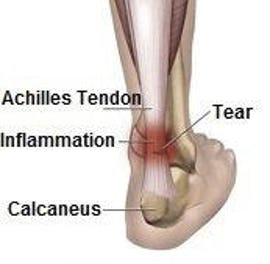

Tendonitis, (also called tendinitis) is the inflammation of a tendon. The part of the tendon known as the watershed zone contains the weakest blood supply. Watershed zones are particularly vulnerable to inflammation and possibly rupture.

Insertional Achilles tendonitis affects the lower part of the heel, where the tendon is attached. Noninsertional Achilles tendonitis refers to fibers in the middle portion of the tendon which have broken down, swollen and thickened.

Bursitis and tendonitis are common types of soft tissue inflammation. These conditions frequently occur in the ankles, knees, elbows, hips, or wrists. Fluid-filled sacs called bursae help bone, muscle, and tendons work smoothly together. Inflammation of one of these sacs is called bursitis. Tendons connect muscles to bones and inflammation of a tendon is called tendonitis. In some cases, the tendon can partially or completely tear.

In the case of tendon rupture, your doctor may recommend surgery. This is often performed in an outpatient setting and typically takes an hour or less. The patient is usually able to return to full activity by six months after surgery, although full recovery may take at least a year.